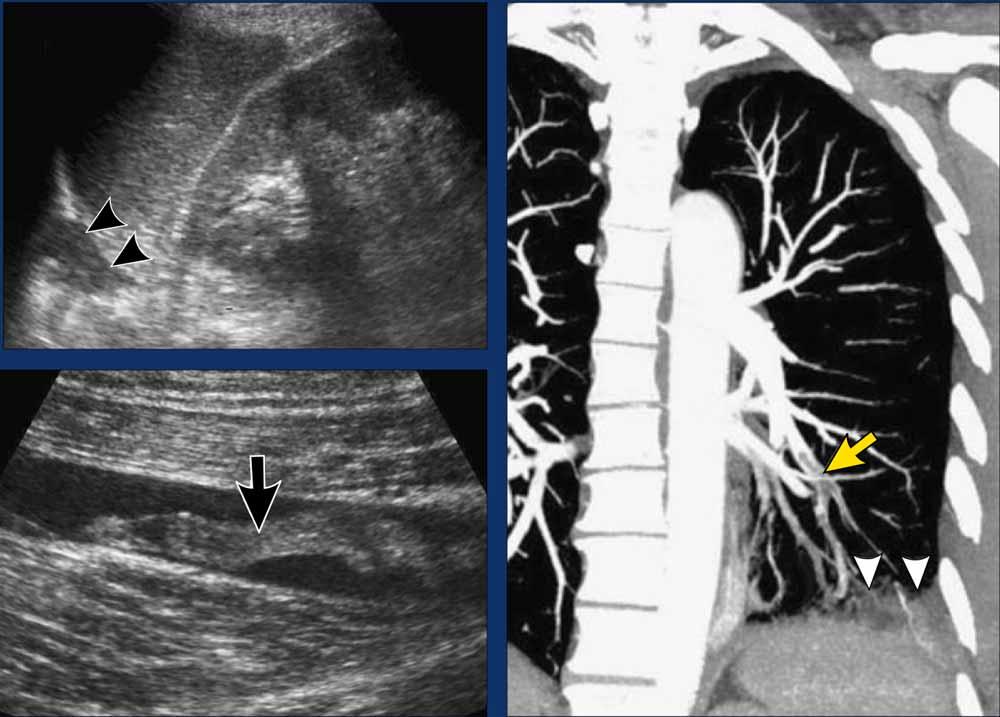

- Hình ảnh CT của một bệnh nhân khác bị chèn ép tim, biểu hiện bằng đau bụng cấp và nôn.

CT không tiêm thuốc cản quang cho thấy tràn dịch màng ngoài tim lượng nhiều với giá trị tỷ trọng cao hơn nước (+35 HU), gợi ý tràn máu màng ngoài tim. Chẩn đoán này được xác nhận bằng chọc hút màng ngoài tim.

Nguyên nhân nền là do mới đặt máy tạo nhịp tim gần đây.

Sau khi dẫn lưu màng ngoài tim, các triệu chứng ở bụng của bệnh nhân đã thuyên giảm.

Bệnh nhân nữ 84 tuổi, gãy xương sườn, nhập viện vì đau cấp tính vùng bụng trên bên phải. Bệnh nhân phủ nhận tiền sử chấn thương.

Hình ảnh học

- Siêu âm cắt ngang đúng tại vị trí đau nhiều nhất cho thấy hình ảnh gãy xương sườn di lệch vừa (mũi tên) kèm theo tụ máu nhỏ (đầu mũi tên). Không phát hiện bất thường nào khác.

- X-quang xác nhận gãy xương cấp tính đầu xa xương sườn 11 phía trước (mũi tên)